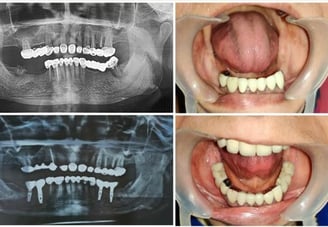

Full mouth implant cases in affordable treatment option

FIX TEETH WITH DENTAL IMPLANTS

Revolutionize Your Smile with Dental Implant